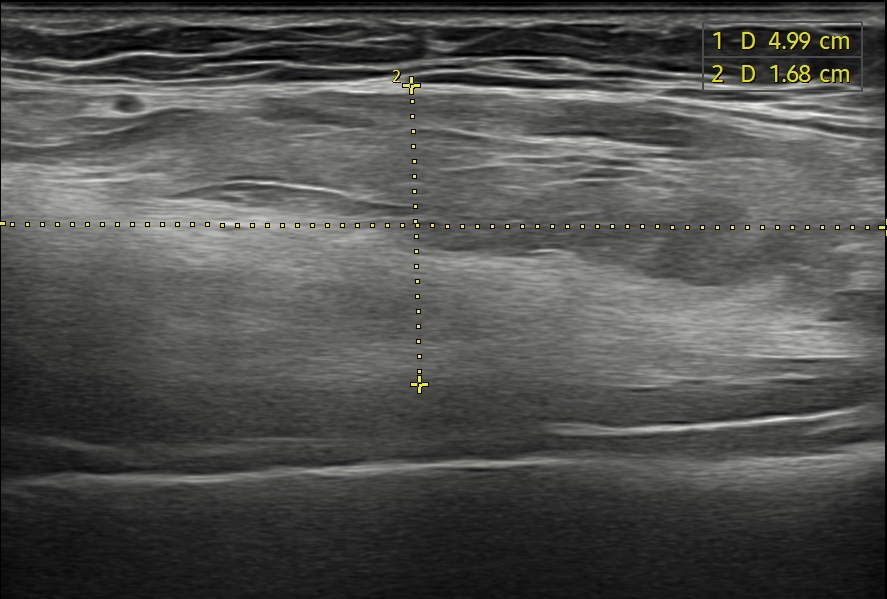

Con el objetivo de caracterizar la lesión, se realiza ecografía clínica.Hallazgos ecográficos

Se objetiva masa bien delimitada, heterogénea, con áreas hipoecogénicas y anecoicas en su interior, de aproximadamente 8 × 2 cm. La lesión parece depender del músculo coracobraquial y no muestra vascularización al Doppler.